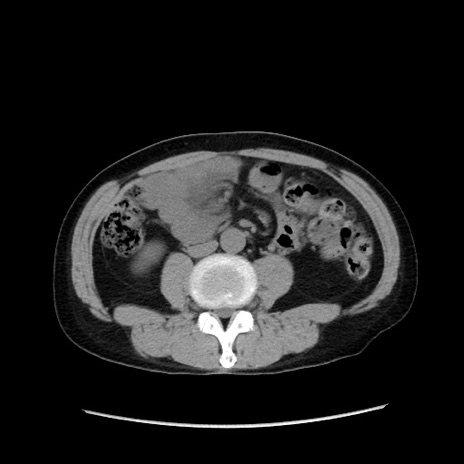

冠状断像

症例37(横断像)

【症例】40歳代 男性

【主訴】腹痛

【現病歴】4時間ほど前に電車に乗車中に臍部上より腹痛出現。徐々に増悪し起立困難となり、救急外来受診。生ものは数日食べていない。今朝お雑煮を食べた。

【身体所見】BT 36.8℃、BP 117/84mmHg、HR 91/min、SpO2 97%、苦悶様、腹部:臍上部広範囲圧痛あり、反跳痛±

【データ】WBC 8100、CRP 0.03